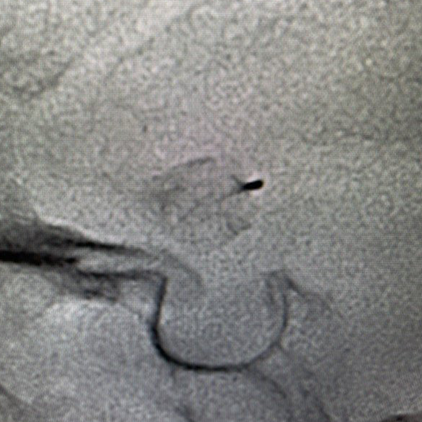

We provide devices and treatment of complex brain aneurysms and vascular malformations free of cost. These are some of the complex brain aneurysm we have recently treated in Pakistan. Devices and catheters used for all procedures were provided by Pakistan Stroke Initiative, and in some cases charges for hospitalization as well.

One of the key components of our stroke center is the Neuroangiography biplane suite. This advanced imaging system enables precise diagnosis and treatment of stroke and brain aneurysms. However, the cost of this technology is substantial, with a single biplane suite costing millions of dollars. Your support will directly contribute to acquiring this life-saving technology and ensuring better stroke treatment for thousands.

Last month, her world changed. She suddenly developed an intense severe headache, the worst imaginable. Throughout the day, she became tired, lethargic, and couldn’t keep anything down. Her parents, a poor laborer and homemaker, took her to the local district hospital, and a CT scan of the head confirmed bleeding in the brain due to a ruptured brain aneurysm.